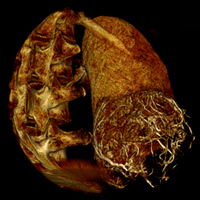

- Функция 3D-DSA позволяет анализировать множественные аневризмы под любым углом

- Благодаря быстрой 3D реконструкции данных на одном изображении можно получить не только изображение сосудов, но и костей, и тканей